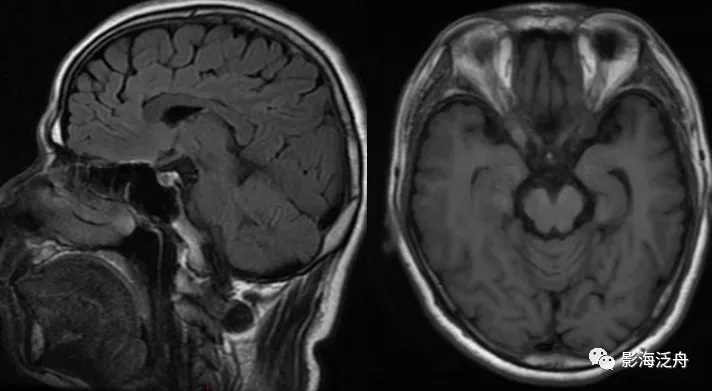

头颅mr t1相

手把手教你基础颅脑mr平扫及后处理